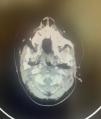

The 22-month-old male and 15-day-old female patients presented with persistent stridor since birth. Tracheoscopy of the first patient revealed a 90% obstructing hemangioma in the subglottic area, while the second patient's CT scan showed a hemangioma at the subglottic level. Both patients were initiated on propranolol therapy. These cases highlight the significance of subglottic hemangioma as a treatable cause of stridor in infants and emphasize the importance of propranolol treatment.